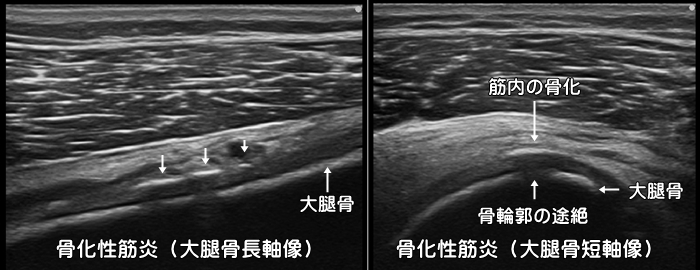

骨化性筋炎(異所性骨化)

サッカーやラグビーなどのコンタクトスポーツで主に大腿の前面を強打(ももかん)すると筋肉内に血の塊である血腫(けっしゅ)が形成されます。その後痛みを我慢して無理に運動したりすることで血腫内にカルシウムが異常に集積し、本来あるはずのない所に骨が作られます。(異所性骨化)筋肉の中に骨ができてしまうと運動時の痛みや圧痛、可動域の制限などが出現します。安静が重要で、重症例ではスポーツ復帰に6ヶ月以上は必要です。レントゲンでは骨化が確認できるまでに1ヶ月程必要ですが、エコーでは早期に確認可能です。